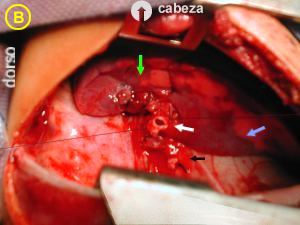

Foto A -

(Cabeza del paciente flecha en circulo)

- Flechas blancas

El lóbulo pulmonar inferior derecho parcialmente colapsado deja notar la presencia de numerosos quistes sub pleural, algo traslúcidos, dando un aspecto característico multi sacular.